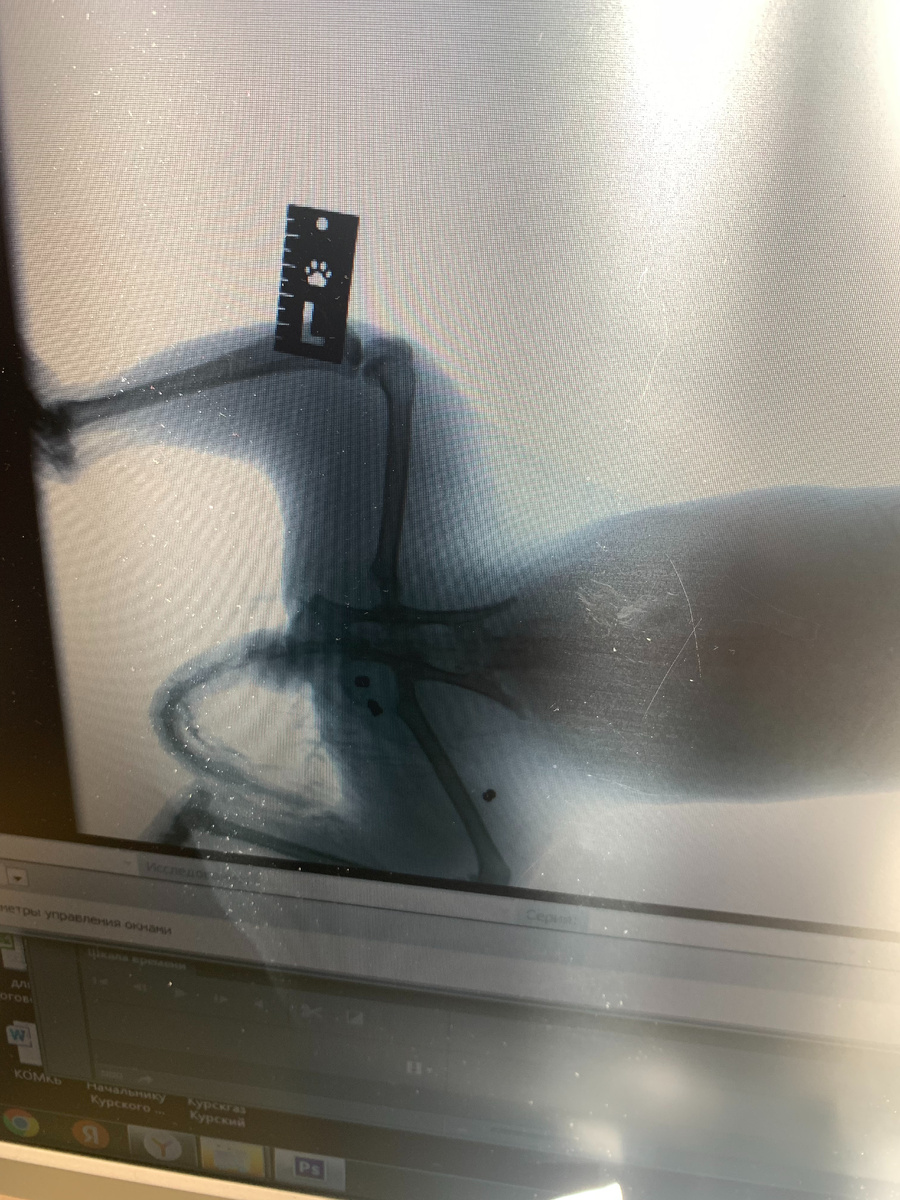

По состоянию сбитого котика.

Из того, что меня пугает : гематома на животе, цвет все темнеет. Если бы не его хороший аппетит и столько сил сопротивляться уколам, было бы страшнее. Такое ощущение что он сам весь сплошная гематома.

По лапкам чувствительность есть..лежит (когда не зол на меня из-за уколов) я его по голове глажу и пузико пытаюсь рассмотреть гематомное, а он лапки вытягивает и на спинку заваливаться пытается.